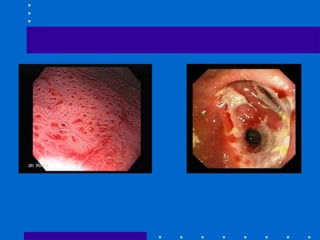

Endoscopy 1.  Upper GI endoscopy  Esophagoscopy, Gastroscopy and Duodenoscopy  To identify  upper GI bleeding, gastric cancer, gastric ulcers, duodenal ulcers useful in detecting tumor, hernia, esophageal strictures Preparation :  NPO 6-8 hrs prior to procedure Anticholinergics(atropine), sedatives are given Remove dentures Lidocaine spray – depress gag reflex Place on left side lying position Post-procedure : NPO until gag reflex returns (2-4 hrs.) monitor vital signs, assess for dyspnea, dysphagia, abdominal pain, fever, bleeding

Gastric Cancer May develop in any part of the stomach but is found commonly at the distal third More common in men and in age 50-70 years old Causes :  heredity, chronic gastric ulcer, chronic gastritis S/Sx:  Gastric distress Flatulence Early satiety Loss of appetite, anorexia Loss of strength and weight loss Dx:  UGIS, absence of HCL – due to destruction of parietal cells by cancer cells Tx:  Gastrectomy, chemotherapy

Gastric Cancer